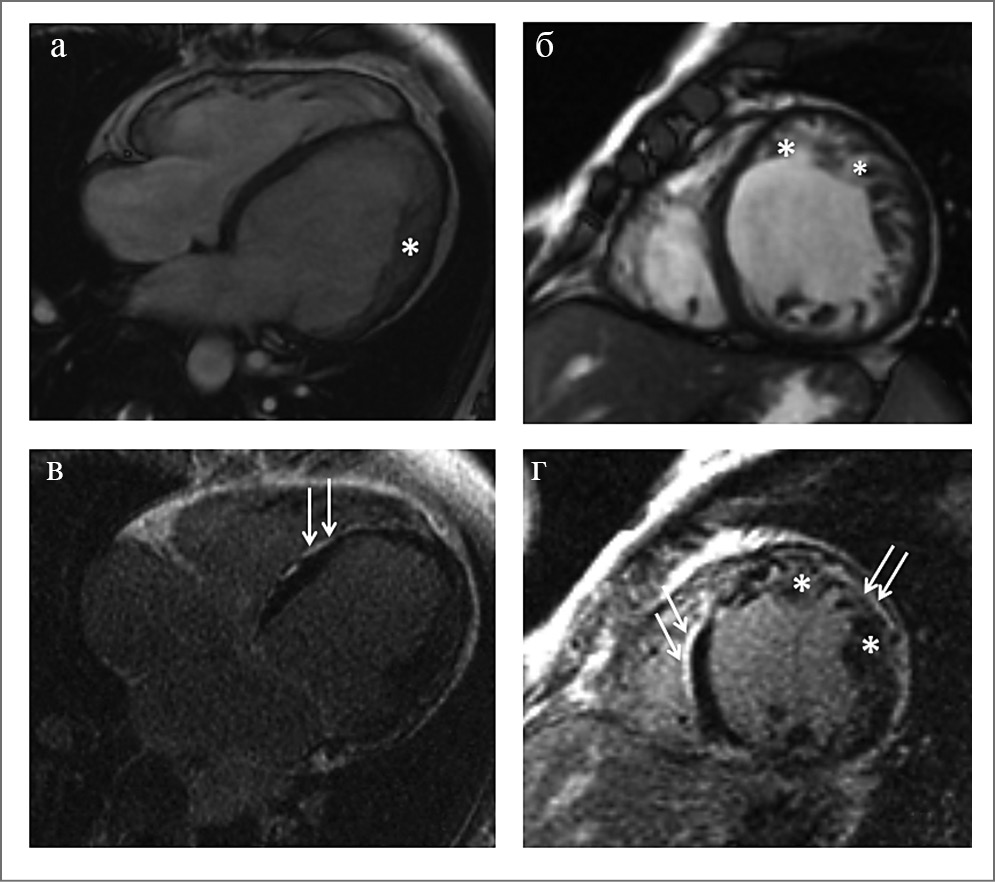

В качестве клинического примера мы представляем пациента 36 лет с тяжелым течением заболевания. По данным МРТ сердца с контрастированием: отмечаются выраженная дилатация левых отделов сердца, двухслойное строение миокарда ЛЖ в верхушке, апикальных сегментах, среднем сегменте боковой стенки, соответствующие критериям некомпактной кардиомиопатии (более чем в 6 сегментах). Толщина компактного слоя в этих сегментах составляет 3–7 мм, некомпактного – 18–22 мм. Некомпактный слой представлен губчатым миокардом. Индексированная масса НМ 40 г/м2, что составляет 26,8% от массы миокарда ЛЖ (при норме до 25%), ФВ 27%. Повышена трабекулярность ПЖ. В области МЖП отмечается гипертрофия миокарда до 15 мм. Также отмечается выраженные фиброзные изменения в миокарде ЛЖ (рис. 5).

Рис. 5, а–в – МРТ сердца в кино-режиме, SSFP-последовательность: а – длинная ось, двухкамерная проекция; б – длинная ось, четырехкамерная проекция; в – короткая ось; *слой НМ толщиной до 20–22 мм; г–е – отсроченное контрастирование, IR-последовательность с подавлением сигнала от миокарда. Стрелки указывают на обширные зоны контрастирования некоронарогенной природы, расположенные субэпикардиально в миокарде передней и боковой стенок ЛЖ, в МЖП со стороны правого желудочка, а также затеки контрастного препарата между трабекулами НМ.